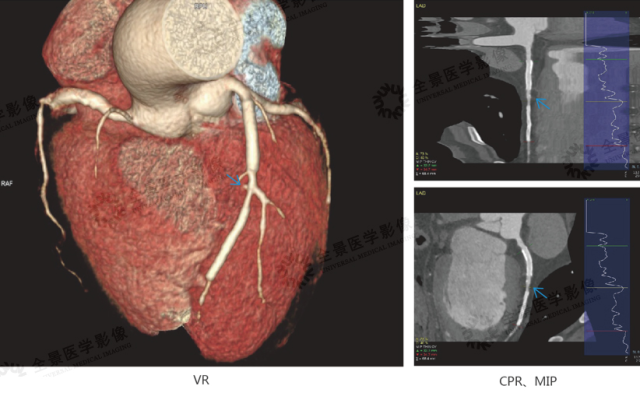

案例 1:冠状动脉 CTA:先天变异

中年男性,病史:平时体健

结论:右冠状动脉未见显示,左回旋支供应原右冠供血区,考虑先天单一冠脉(2 型)